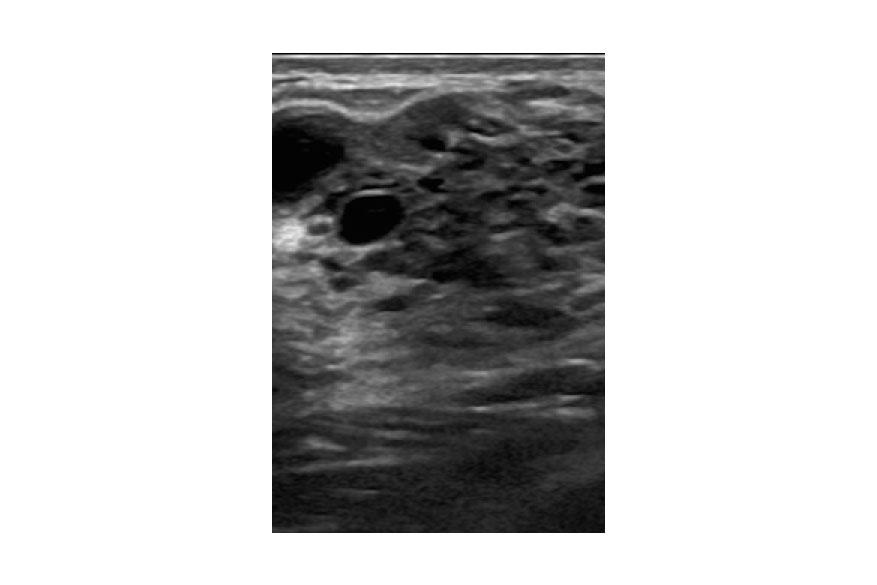

Ένα ενδοπορικό θήλωμα( Intraductal Papilloma ) είναι ένας μικρός, καλοήθης όγκος που σχηματίζεται σε έναν γαλακτοφόρο πόρο στο στήθος. Αυτοί οι όγκοι αποτελούνται απο αδένα, ινώδη ιστό και αιμοφόρα αγγεία. Εμφανίζονται συχνότερα σε γυναίκες ηλικίας 35 έως 55 ετών. Δεν υπάρχουν γνωστοί παράγοντες κινδύνου για τα ενδοπορικά θηλώματα.